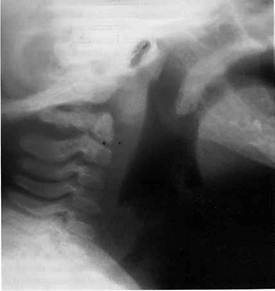

En la LT no complicada no es aconsejable realizar estudios de laboratorio y gabinete por ser su diagnóstico básicamente clínico.6,17 Por ello, la evaluación radiológica no es necesaria y solo debe ser considerada en situaciones específicas: a) en un niño con síntomas atípicos; b) si el diagnóstico no es claro; c) ante la sospecha de aspiración de cuerpo extraño; y d) cuando la respuesta al tratamiento usual no es satisfactoria.22 Cuando se realiza una radiografía anteroposterior de cuello, la imagen característica de la LT es una sombra o estrechamiento de la tráquea en el área subglótica (signo de “la aguja, en reloj de arena o del campanario”) de 5 a 10 mm que confirma el diagnóstico (figura 2). En la proyección lateral o de perfil del cuello puede observarse una sobre distensión de la hipofaringe y un estrechamiento por debajo de las cuerdas vocales que ayuda a descartar epiglotitis, absceso retrofaríngeo y aspiración de cuerpo extraño (figura 3). Cuando se realizan los estudios radiológicos, el niño debe ser monitorizado de cerca por un personal con habilidades y experiencia en el manejo de vías aérea difícil. Sin embargo, su realización se halla contraindicada cuando hay signos de obstrucción inminente.11,25 El valor diagnóstico de estos hallazgos radiográficos es cuestionable, porque no se observan en todos los casos de LT viral y se ha demostrado que su sensibilidad y especificidad son muy bajas para confirmar o descartar esta enfermedad.11

Figura2. El clásico signo de “la aguja”